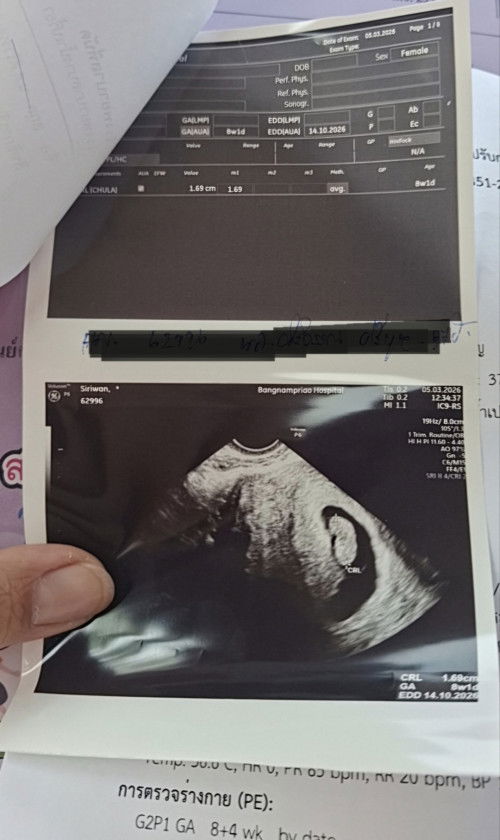

อยากทราบเพศลูกค่ะ

เรามีอาการแพ้แบบเบื่ออาหาร พะอืดพะอม ไม่อยากอะไรเลย ง่วงนอน ขี้เกียจ แต่สวยดูมีออร่า แบบนี้ได้ลูกสาวรึลูกชายค่ะ